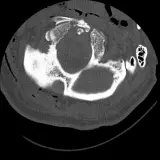

Over 2,100 interactive radiology cases, curated by radiologists for your level of training. Scroll, window, and view cases full screen โ€” just like on PACS. Click linked findings in each writeup to jump straight to them on the image. Cases include sample reports, a focused discussion section, original illustrations, and videos.

Casi completamente interattivi con gli strumenti che ti aspetti su un PACS: scroll, windowing, zoom, pan, misurazioni, ROI e modalitร  a schermo intero.

Annotazioni dettagliate evidenziano i reperti chiave direttamente sui casi. Clicca sui reperti collegati nella descrizione del caso per saltare alla loro esatta posizione sullo scan.